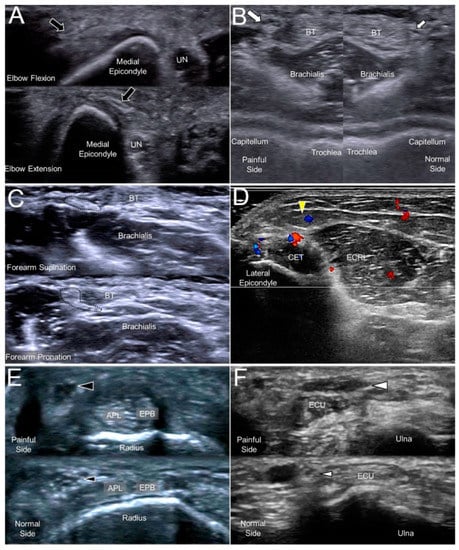

The most common causes of MACN injury are iatrogenic, e.g., venous punctures, injections for medial epicondylitis, or cubital tunnel releases. A subcutaneous lipoma could also be the culprit of MACN entrapment [14]. Repeated flexion and extension of the elbow (like shaking a rug) could place the nerve under the risk of overstretching [15]. When scanning patients with MACN neuropathy, evoking Tinel’s sign by sonographic palpation is paramount as well as a dynamic examination of the flexed and extended elbow (Figure 3A, Supplementary Video S3). In most cases with suspicion of MACN entrapment, the nerve might not present an overt change in the sonography, and a sono-Tinel sign combined with a guided nerve block would be required to confirm the diagnosis.

5.3. Clinical Implication

The close anatomical relationship between the LACN and the cephalic vein renders the nerve vulnerable to iatrogenic injuries. Traumatic nerve injury during venipuncture is the main cause of LACN neuropathy. The nerve can be damaged by direct needle touch or compression by an adjacent hematoma/thrombosis. As the LACN is located next to the distal biceps tendon, the second most common etiology is related to distal biceps tendon tears. Another less common cause is a compression by a cast used to immobilize fractures near the elbow joint. When the LACN is injured, it typically appears enlarged in US imaging (Figure 3B), and its echogenicity might increase due to hemorrhage inside the nerve [17]. A dynamic examination (during supination/pronation of the forearm) can also contribute to the identification of problems related to distal biceps tendon-related problems (Figure 3C, Supplementary Video S4).

6.3. Clinical Implication

The posterior branch of the PACN is in proximity to the lateral epicondyle and may be irritated in cases with chronic lateral epicondylitis (Figure 3D). Dellon et al. reported that the PACN might be entrapped by scar tissue or that a neuroma may develop after lateral epicondylitis surgery [20]. In patients with recalcitrant lateral epicondylitis, US-guided injection and/or radiofrequency ablation can be considered as alternative approaches for better pain relief.

7.3. Clinical Implication

A compressive neuropathy of the SBRN is also named Wartenberg’s syndrome. The causes of nerve entrapment include compression by a bracelet, watch, or handcuff and irritation from an adjacent metal implant. An SBRN neuropathy is also associated with de Quervain’s tenosynovitis (Figure 3E) [22]. Therefore, in idiopathic cases of neuropathy, the abductor pollicis longus and extensor pollicis brevis should also be scrutinized for concomitant tendon and surrounding sheath pathology.

8.3. Clinical Implication

The risks of DCBUN neuropathy are similar to those of SBRN, e.g., compression by a bracelet or a metal plate fixed over the distal forearm. Like the association between the SBRN neuropathy and de Quervain’s tenosynovitis, DCBUN neuropathy is associated with extensor carpi ulnaris tenosynovitis [25]. Therefore, in a patient with non-traumatic DCBUN neuropathy, this tendon should be routinely scanned to search for possible causes, such as a swollen tendon/sheath. In traumatic cases, the sonographer may run into a DCBUN neuroma adjacent to the scar tissue (Figure 3F).

Figure 3. A snapped medial antebrachial cutaneous nerve (black arrow) in a woman complaining of forearm pain (A). A swollen lateral antebrachial cutaneous nerve (big white arrow) compared to the nerve of the asymptomatic side (small white arrow) in a woman with forearm pain (B). A lateral antebrachial cutaneous nerve (dotted circle) entrapped by the distal biceps tendon during elbow supination/pronation (C). A posterior antebrachial cutaneous nerve (yellow arrowhead) with peripheral hypervascularity in a male with chronic lateral epicondylitis (D). A swollen superficial radial nerve (big black arrowhead) compared to the nerve on the asymptomatic side (small black arrowhead) in a man with de Quervain’s tenosynovitis (E). A neuroma of the dorsal ulnar cutaneous nerve (big white arrowhead) and the normal contralateral nerve (small white arrowhead) in a man with a fracture of the 5th metacarpal bone (F). UN, ulnar nerve; BT, biceps tendon; CET, common extensor tendon of the wrist; ECRL, extensor carpi radialis longus muscle; APL, abductor pollicis longus tendon; EPB, extensor pollicis brevis tendon; ECU, extensor carpi ulnaris tendon.